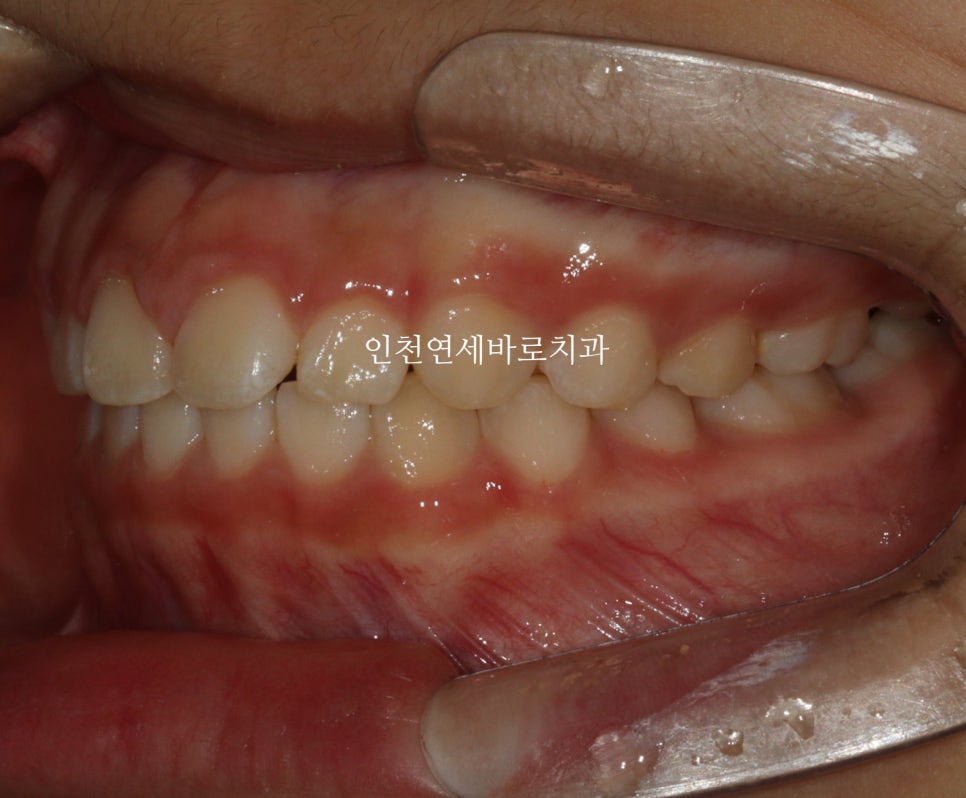

14주 후: 치료 결과

거의완성되었습니다.

거의 라고 말하는 이유는 저희 의료진 눈에는 아주아주 미세한 부분이 마음에 들진 않아서요.

인비절라인 라이트는 1년이라는 기간안에 1회 재제작이 아주 저렴한 비용으로 가능합니다.

이 친구도 정기검진을 하고 25.1.월쯤 아주미세한 부분의 수정을 위해 재제작을 하기로 했어요.

화살표 부분이 약간 아쉬웠기 때문입니다.

저런건 4주정도면 충분하죠.

조금 더 활짝 웃게 된 아이입니다.